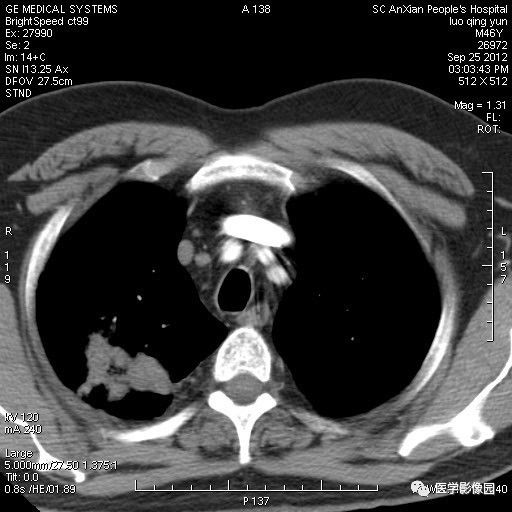

影像学表现:右上肺见不规则团块状高密度阴影,略有分叶级毛刺,边缘模糊,邻近胸膜增厚,增强扫描呈轻中度强化。

诊断结果:右上肺炎性假瘤

本病影像学表现无绝对特征性。单发多见,多位于肺表浅部位,多呈圆形或椭圆形,直径多在2-5cm或更大;多有假包膜,边缘多清晰光整,有时也毛糙,并可有分叶或毛刺;邻近胸膜局限性增厚、牵拉,病灶边缘呈桃尖样突起即桃尖征(尖端指向胸膜);增强扫描多呈中度均匀强化,持续时间较长。亦可显著强化。